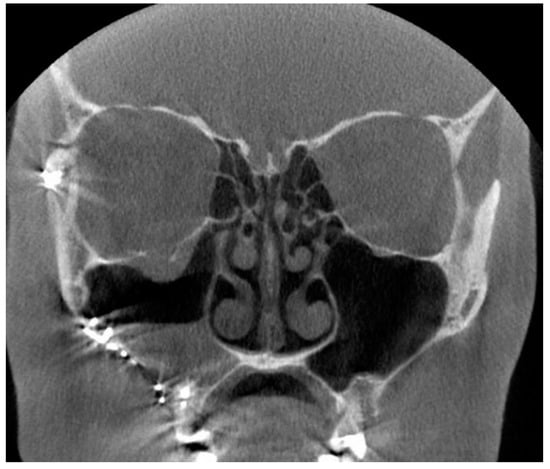

Figure 2. The coronal (A) and sagittal (B) slices of the CBCT image present sinusitis and distinct apical periodontitis of the root-filled right maxillary molar D16 buccal roots (arrow).

In total, 214 patients with CBCT images taken during 2017 were identified with a diagnosis of CRS. Of these patients, 139 were women (65%) and 75 were men (35%), with a median age of 62 years and with a range from 50 years to 89 years. Seven reports of the CBCT images were missing. Based on the reports, CRS of dental origin was suspected in 24/214 (11%) of the CBCT images due to AP diagnosed in the upper jaw (Figure 2). Artifacts were recorded in the reports in only four images, and an additional X-ray imaging examination was recommended twice due to the artifacts.